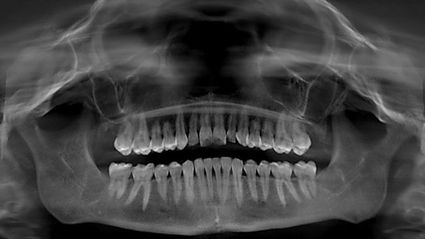

Mein Weg zu Swiss Biohealth war lang und verschlungen. Ich entdeckte zum ersten Mal im Alter von 21 Jahren, dass ich Kavitationsinfektionen hatte, als ich zum ersten Mal einen biologischen Zahnarzt in Seattle aufsuchte, als ich noch Student an der nahe gelegenen Bastyr University war. Der biologische Zahnarzt in Seattle machte ein digitales Panoramaröntgenbild meines Mundes, das zeigte, dass ich Löcher in meinem Kiefer hatte, die mit nekrotischem Material gefüllt waren, das von der Weisheitszahnentfernung in der Highschool übrig geblieben war. Das Bild unten ist das digitale Panoramaröntgenbild meines Mundes, das zur Diagnose der Kavitationen verwendet wurde. Sie können die Umrisse der Löcher in den unteren linken und rechten Ecken meines Kiefers sehen. Die Kavitationen im oberen Teil meines Kiefers sind viel schwieriger zu erkennen, aber sie waren auch kleiner als die im unteren Bereich.